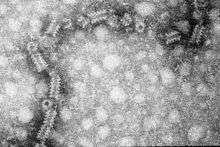

| TEM micrograph of a mumps virus particle. | |

Electron microscopy (EM) revealed that the mumps virus (MuV), like other members of the Paramyxoviridae, has an enveloped virion of roughly spherical or pleiomorphic (variable) shape.[2] Paramyxovirus particles can have sizes ranging from 120–450 nm in diameter.